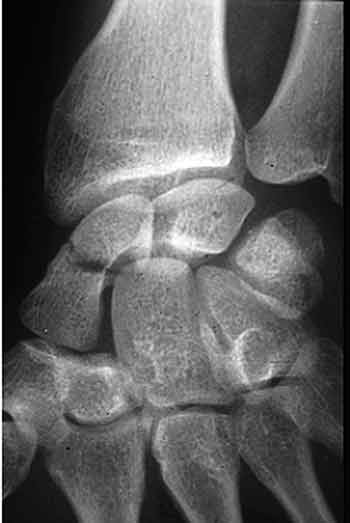

Mise au point Fracture du scaphoïde : Pourquoi je crois qu'il faut souvent les opérer ? , Timothy Herbert Mons, France N°105 - Juin 2001 ● 8 min de lecture